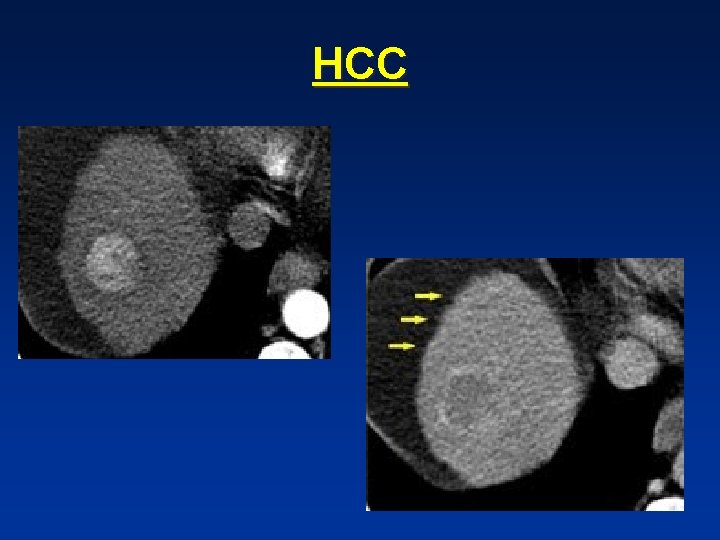

• Cirrhotic liver with hypervascular , inhomogenous lesion. • The inhomogenous enhancement and partial capsule are helpful for the diagnosis of HCC

• Small HCC in cirrhotic liver not visible on NECT , clearly visible on arterial phase, and not visible in portal venous phase

• HCC in cirrhotic liver , notice fast wash out in equilibrium phase compared to surrounding liver parenchyma